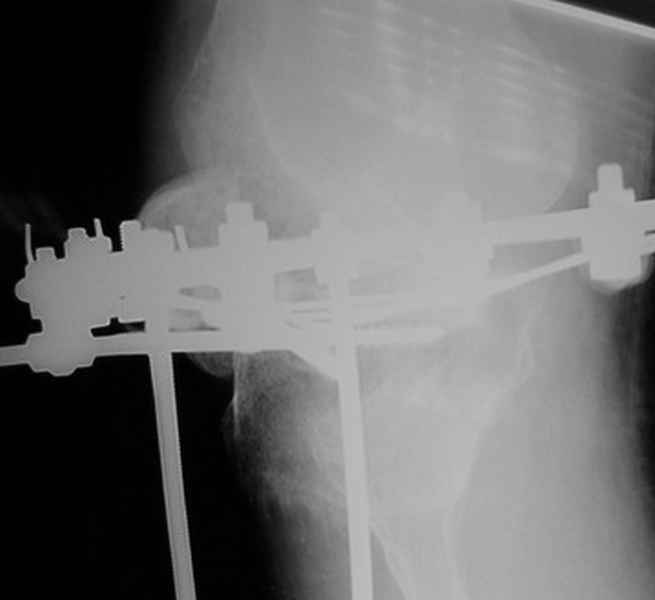

Пациент В. 53 лет, травма в феврале 2009. ДЗ. Открытый оскольчатый перелом нижней трети голени. При боли поступлении выполено ПХО, аппарат Илизарова. В последующем проводили ВХО, резекция костных отломков, укорочение 6 см, рана зажила. Была выполнена остеотомия большеберцовой кости в проксимальном отделе, резекция. Производилось тракция. На последних рентгенограммах выявлено, что одновременно с "выращиванием" регенерата произошло низведение надколенника на длину выращенного регенерата. Клинически: активное разгибание сохранено, объем движений в колене 180-110 градусов. Черными стрелками обозначен верхний край надколенника с одной и с другой стороны. Красная стрелка обозначает пальпируемую связку надколенника. Причина - остеотомия выше места прикрепления связки надколенника. Вопрос: была ли у кого подобная ситуация? Что делать? При первом обдумывании приходит решение: отсечение места прикрепления связки надколенника с костным блоком, перемещение на "правильное" место, укорочение сухожилия четырехглавой мышцы.

По снимкам - плотность регенерата хорошая, сложностей с фиксацией в него костного "основания" быть не должно.

К сожалению, подобное осложнение "нет-нет да и возникает" при удлинении, коррекции деформации голени. В англоязычной литературе оно описано как "patella baja". Один из вариантов лечения - проксимальное перемещение надколенника приемами чрескостного остеосинтеза.